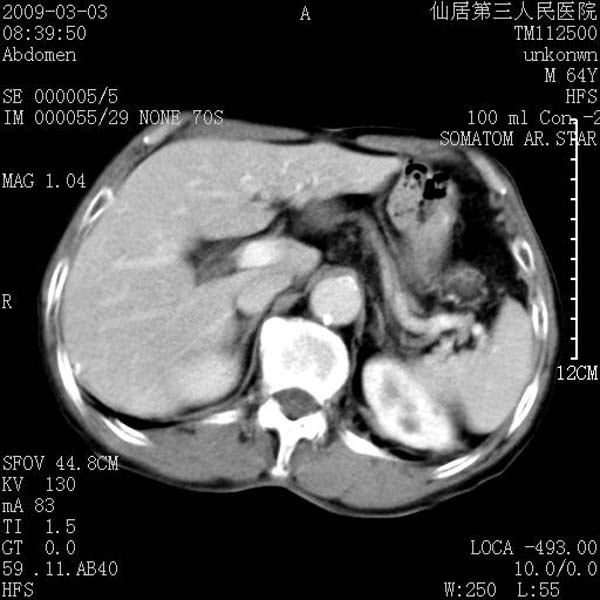

标题: CT18469:男性,64y,体检B超示肝脏低回声肿块,有胃溃疡手术 [打印本页]

患者,男性,64y,体检b超示肝脏低回声肿块,有胃溃疡手术史。

考虑----胃肠道间质瘤可能性大

从平扫及增强的特点来看,支持肝脏腺瘤并出血。

考虑胃间质瘤可能性大。

胃肠道间质瘤!

考虑十二子肠术后改变,建议钡餐检查。

ct值呢?感觉没强化,象囊性。

考虑肝静脉韧带裂区良性占位性病变(囊肿?)。

考虑肝囊肿并出血可能性大.

考虑高密度囊肿可能性大